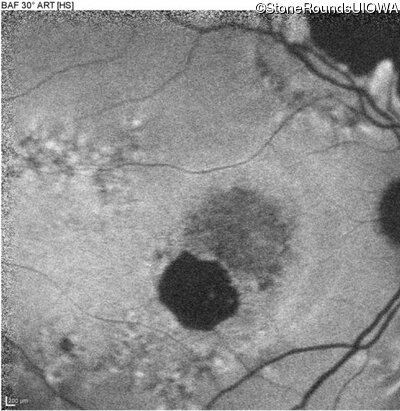

Blue Autofluorescence - Right - 20/125 -2

Exemplar

Blue Autofluorescence - Left - 20/125 +2